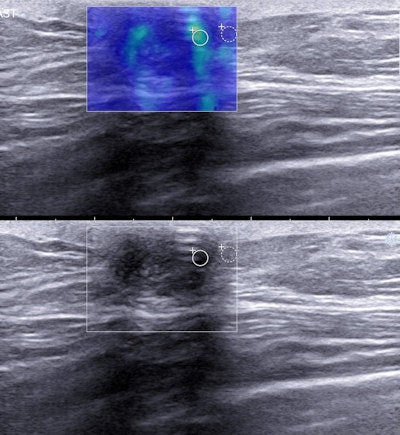

The team's retrospective study compared shear-wave elastography (SWE) features of 26 triple-negative breast cancers with 32 tumors that were not. The researchers found that the triple-negative cancers often are softer on SWE and have a lower lesion-to-fat stiffness ratio compared with the other, more common types of invasive breast cancers (European Radiology, 1 August 2015).

The results demonstrate triple-negative breast cancers most commonly present as red (stiff), but a significant proportion of tumors appear as blue or green (soft), as well as orange. However, invasive cancers that are not triple-negative almost exclusively present as red.

Triple-negative lesions | 42.3% | 15.4% | 3.8% | 19.2% | 19.2% |

Nontriple-negative lesions | 93.7% | 3.1% | 3.1% | 0% | 0% |